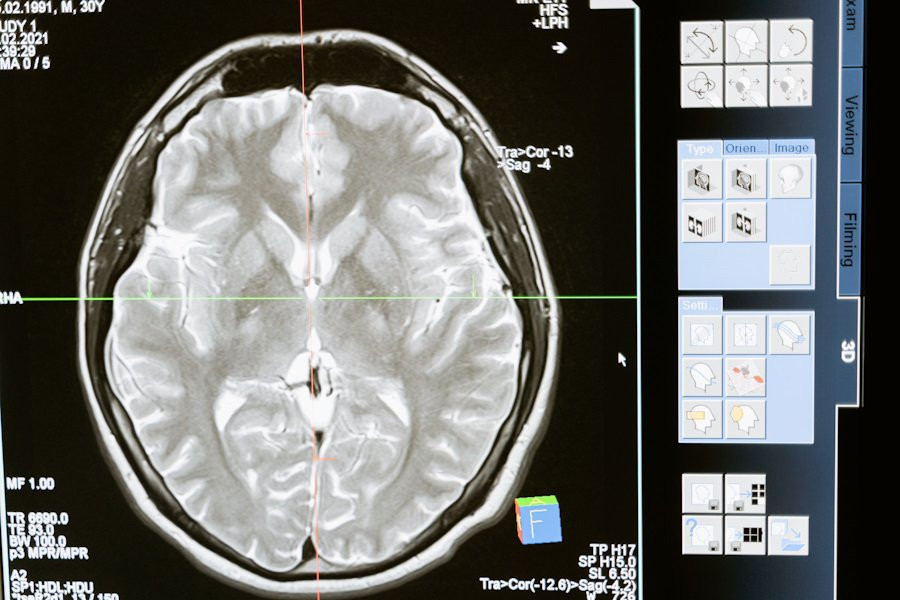

Ученые сделали важный шаг в понимании того, как мозг интегрирует информацию во время сложных когнитивных процессов, таких как чтение. В новом исследовании, проведенном в University of California, было обнаружено, что нейроны в различных областях мозга синхронизируются, когда человек читает и принимает семантические решения.

Результаты этого исследования опубликованы на портале Nature. Исследователи использовали внутричерепную электроэнцефалографию (ЭЭГ) для наблюдения за активностью мозга у участников эксперимента.

Основное открытие заключается в том, что высокочастотные колебания (~90 Гц) в нейронах синхронизируются с высокой точностью, когда мозг объединяет информацию из разных областей во время чтения. Эти ко-пульсации, или синхронизированные всплески активности, усиливаются в момент, когда мозг связывает визуальную информацию со смыслом и формирует осознанное понимание прочитанного.

Исследование показало, что такие ко-пульсации происходят в течение 200–400 миллисекунд после начала слова, а затем усиливаются в течение 400–800 миллисекунд, когда мозг обрабатывает семантические значения слов. Эти синхронизированные всплески активности наблюдались на значительных расстояниях между различными областями мозга, что подчеркивает их важность для интеграции информации.